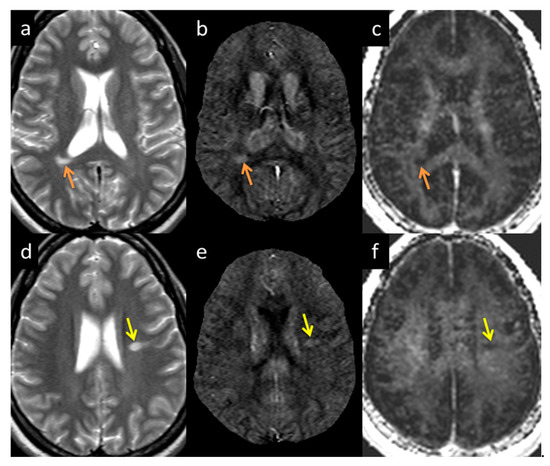

3.3. QSM ± Lesions